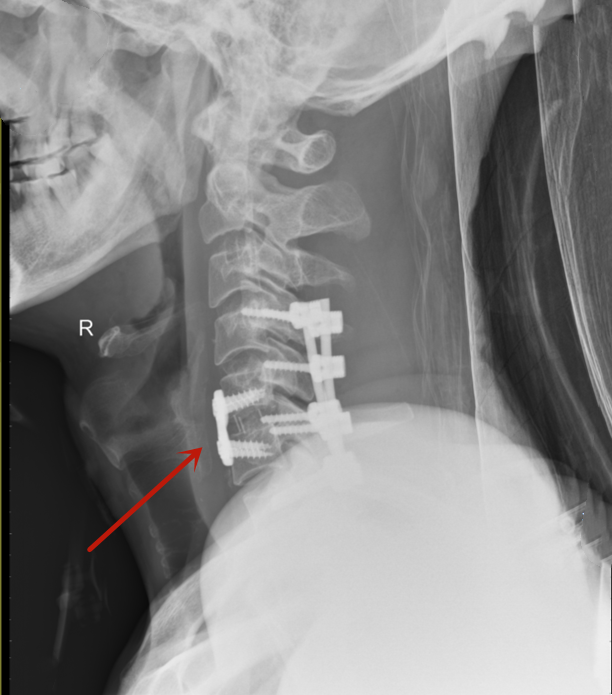

术后影像资料

患者男性,66岁,不慎滑倒后从1米高台阶处跌落摔伤,颈部着地,颈部疼痛难忍并伴有双上肢麻木等症状,紧急入院,给予对症处置后行颈椎X线片、三维CT、MRI及颈部血管CTA等辅助检查,结合检查检验结果,诊断为创伤性颈椎骨折脱位、颈髓损伤、颈6椎体骨折、颅脑损伤。经科室讨论评估后,于2月21日由急救中心副主任成鹏在全麻下成功实施颈椎前路切开复位、C5/6椎间植骨融合、前路钢板内固定术+颈椎后路螺钉系统内固定术,术后恢复良好,四肢肌力恢复正常,现已康复出院。本例手术的成功救治,标志兰大二院急诊外科在严重、复杂脊椎创伤救治方面又上了新台阶。